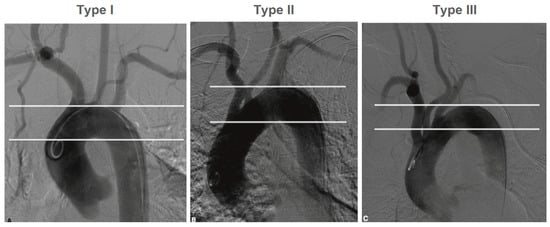

- Aortic arch type: type I and II (Figure 1);

Figure 1. Type I, II and III aortic arch.

Type II AA was found 20% more frequently than type I AA. The angle between the AA and the supra-aortic vessel varied depending on the type of AA and the side of the lesion. Type I AA and right-sided lesions were associated with larger angles, whereas type II AA and left-sided lesions were associated with smaller angles.

The perioperative incidence of stroke and death was lower in this study than in the RCTs that compared CAS against CEA for both symptomatic and asymptomatic patients. Based on our results, anatomical criteria should be taken into account when determining the indication for CAS. For cannulating the CCA, the angle between the AA and the supra-aortic vessel, as well as the AA-type, play very important roles. The AA changes over time, and these changes are caused, among other things, by atherosclerosis, arterial hypertension, and age. AA remodeling results in elongation of the AA and caudal positioning of the supra-aortic vessels [20]. At the same time, the difficulty of cannulating the supra-aortic vessels increases parallel to the AA-type, and simultaneously with an increased risk of embolization due to the required manipulations in the AA [21,22]. In our institution, a type III AA is considered a contraindication for transfemoral cannulation of the carotid artery.